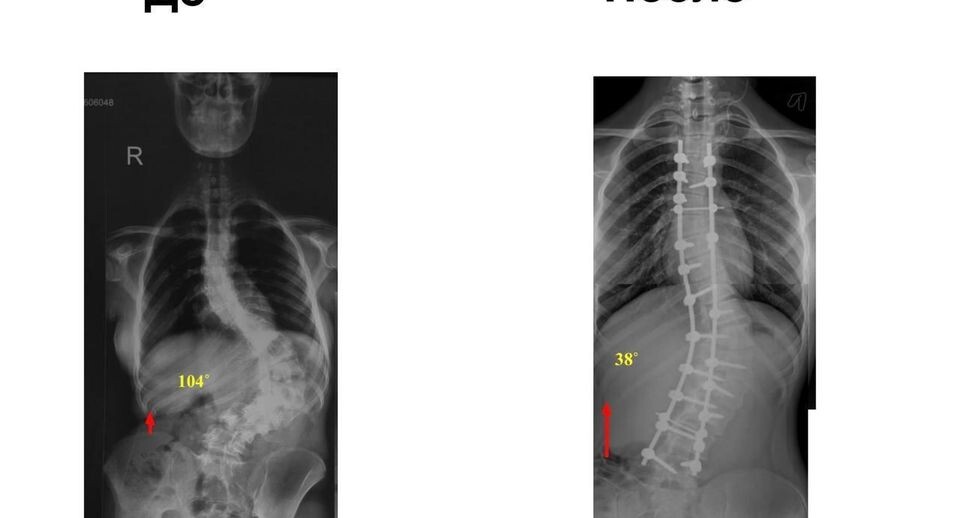

Подростка со сколиозом 4-й степени спасли в медцентре Рошаля

В Детский клинический центр им. Л. М. Рошаля поступила 14-летняя девушка. Ее беспокоили боли в спине и деформация позвоночника. После обследования врачи поставили диагноз «сколиоз четвертой степени». Хирургическое вмешательство проводили под нейрофизиологическим мониторингом. Врачи установили 20 титановых винтов, их подбирали специально под пациентку. После чего специалисты устранили деформацию, это вернуло позвоночнику девочки подвижность. Для закрепления хирурги установили специальные стержни и наложили швы. Операция прошла успешно. «В результате выпрямления позвоночника девушка «выросла» на 11 сантиметров», — отметил заведующий отделением травматологии и ортопедии № 2 Алексей Иванов. Сейчас пациентка проходит курс реабилитации, скоро ее выпишут. После полного восстановления девушка сможет жить обычной жизнью. Автор: Александра Ляпина

В Детский клинический центр им. Л. М. Рошаля поступила 14-летняя девушка. Ее беспокоили боли в спине и деформация позвоночника. После обследования врачи поставили диагноз «сколиоз четвертой степени».

Хирургическое вмешательство проводили под нейрофизиологическим мониторингом. Врачи установили 20 титановых винтов, их подбирали специально под пациентку. После чего специалисты устранили деформацию, это вернуло позвоночнику девочки подвижность. Для закрепления хирурги установили специальные стержни и наложили швы.

Операция прошла успешно.

«В результате выпрямления позвоночника девушка «выросла» на 11 сантиметров», — отметил заведующий отделением травматологии и ортопедии № 2 Алексей Иванов.

Сейчас пациентка проходит курс реабилитации, скоро ее выпишут. После полного восстановления девушка сможет жить обычной жизнью.